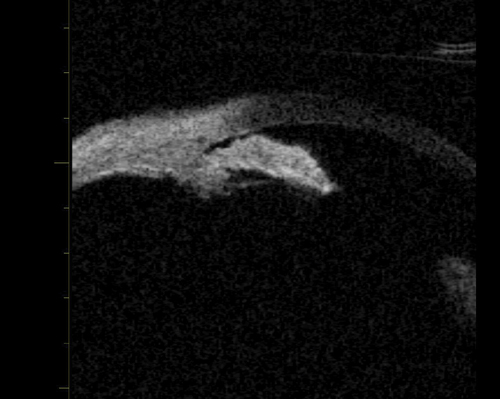

A large or anteriorly subluxated lens, especially in a small eye, may result in phacomorphic angle closure. The lens pushes the iris forward resulting in angle closure and obstruction of the trabecular meshwork. (Figure 3). Lens swelling may result from an intumescent cataract, traumatic injury or simply an age related thickening of the lens in small eyes. In such cases, cataract surgery is usually required. UBM may be used to visualise the lens size and position and to evaluate the iris configuration (Figure 3b).

Figure 3a: Phacomorphic glaucoma. Axial image of anterior segment.

This shows that the anterior chamber is shallow and the iris has a markedly elevated lens vault

caused by a thickened and anteriorly positioned lens. The iris has significant irido lenticular contact.

Figure 3b: Phacomorphic glaucoma. Lenticular profile where the iris follows the shape of the anterior surface of the lens.

Elevation of the lens vault (height of the anterior lens capsule above the sulcus plane) greater than 600 microns is an indication of a potential phacomorphic mechanism. A lens thickness to axial length ratio of >20% is also a risk factor for phacomorphic angle closure, and therefore A or B scan axial length measurements are recommended, as well as UBM in assessing angle closure cases.